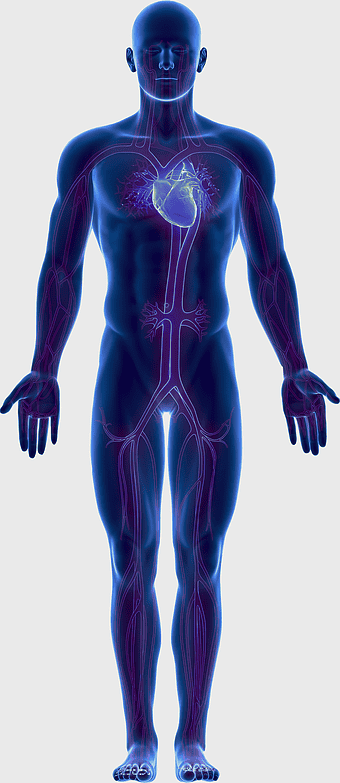

human circulatory system, blood vessel anatomy, weight loss exercise benefits, heart and artery health, vascular network visualization, cardiovascular health illustration, systemic circulation diagram -

human circulatory system diagram, blood vessel network illustration, human anatomy chart, cardiovascular system overview, human body medical illustration, physiological system depiction, organ function visualization -